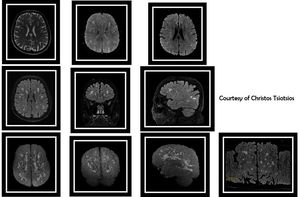

High-resolution MR Imaging of chronic microvascular ischemic disease (multiple T2 hyperintense foci), based on volumetric acquisitions (3D T2, 3D T2 FLAIR & 3D SWAN are shown here) and SS-EPI DWI with b0, b500 & b1000. In addition, figure shows 3D MIPs and curved MPR of the volumetric FLAIR acquisition for quantification purposes.